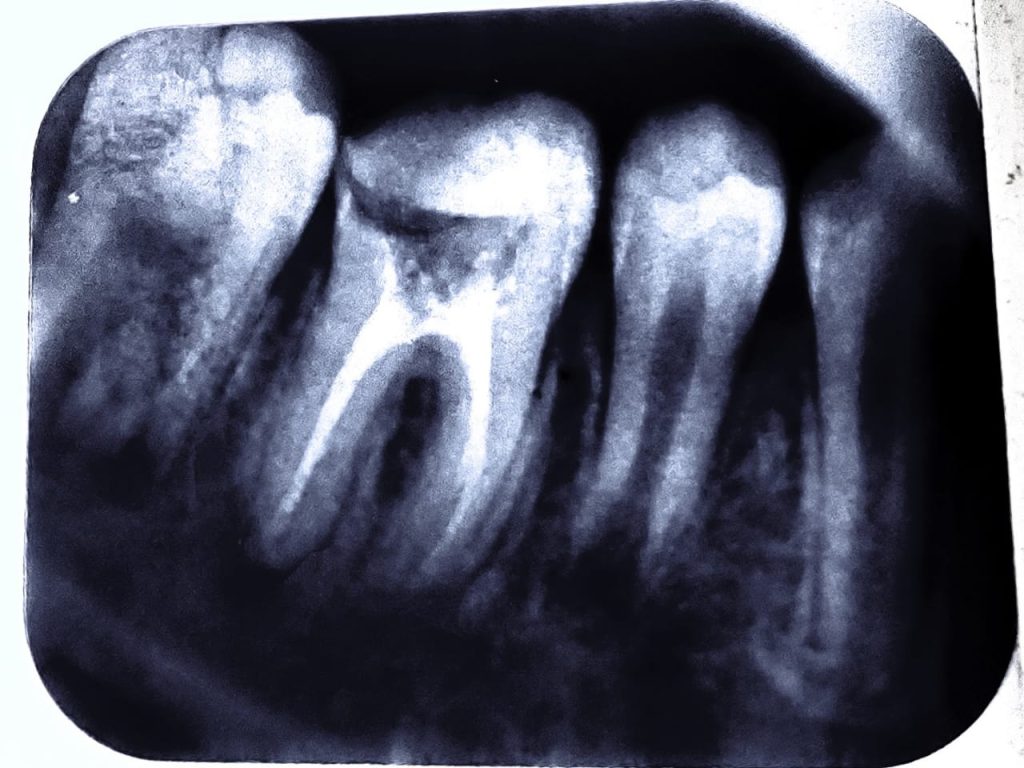

Radiograph:

radiograph shows periapical radiolucency with no apex formation in mesial and distal roots.